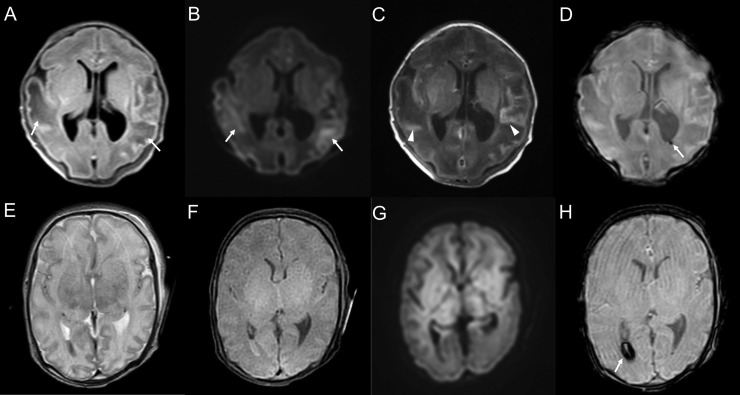

All the nine neonates with neurological abnormalities had abnormal neuroradiological findings. The neuroradiological characteristics of the nine neonates are summarized in Table 2. Of the nine neonates with neuroradiological abnormalities, seven were in the Sym-M-N group. All the neonates with neurological abnormalities developed respiratory failure that needed NICU admission. Of these, four (44.4%) were very preterm and two (22.2%) were preterm. The most common imaging feature was intracranial hemorrhage (germinal matrix hemorrhage, n = 2 [22.2%]; parenchymal hemorrhage, n = 2 [22.2%]; intraventricular hemorrhage, n = 1 [11.1%]), followed by hypoxic brain injury (diffuse white matter and magnetic resonance spectroscopy abnormalities, n = 2 [22.2%] each; FIGURE 1, FIGURE 2, FIGURE 3 ). Patient 5, with a right frontal lobe hematoma, was diagnosed with holoprosencephaly, and patient 6, with hypoxic-ischemic injury (HIE), was born to a mother with placental abruption.

FIGURE 1.

Representative cases with ultrasound abnormalities. A 28-weeks-and-0-day-old female born to a coronavirus disease 2019 (COVID-19) symptomatic mother (patient 2). The neonate had very low birth weight and respiratory distress syndrome. She showed decreased muscle tone and decreased activity. Ultrasound on the first day after birth shows a high-echoic lesion in the left caudate nucleus, indicating a grade 1 germinal matrix hemorrhage (A and B; arrows). A 31-weeks-and-1-day-old female, born to a COVID-19 symptomatic mother (patient 3). The neonate had meconium aspiration syndrome and low birth weight. She was hypotonic and floppy. Ultrasound on the first day after birth shows decreased sulcation indicating prematurity and ventriculomegaly (C and D). A 24-weeks-and-0-day-old male born to a COVID-19 symptomatic mother (patient 1). The neonate had neurobehavioral instability. Ultrasound on the first day of birth shows a high-echoic lesion, indicating hemorrhage in the right caudate nucleus (E, arrow) and germinal matrix (F, arrows).